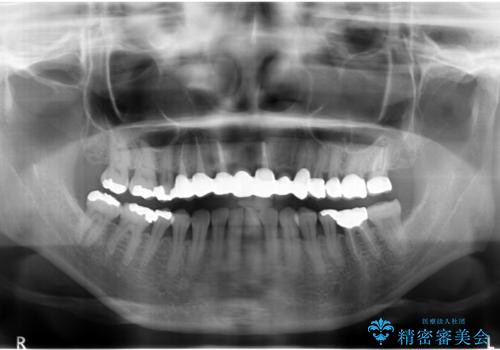

- 若い時に作った前歯のブリッジがの根元が黒くなってきているとのことで来院。

支える歯が1本虫歯がひどく、割れていました。

根の治療からやり直して新しいブリッジにしています。

ブリッジの支台歯は、根の再治療を含めて行なっています。

下の歯は、患者様の希望によりホワイトニングを行なっています。